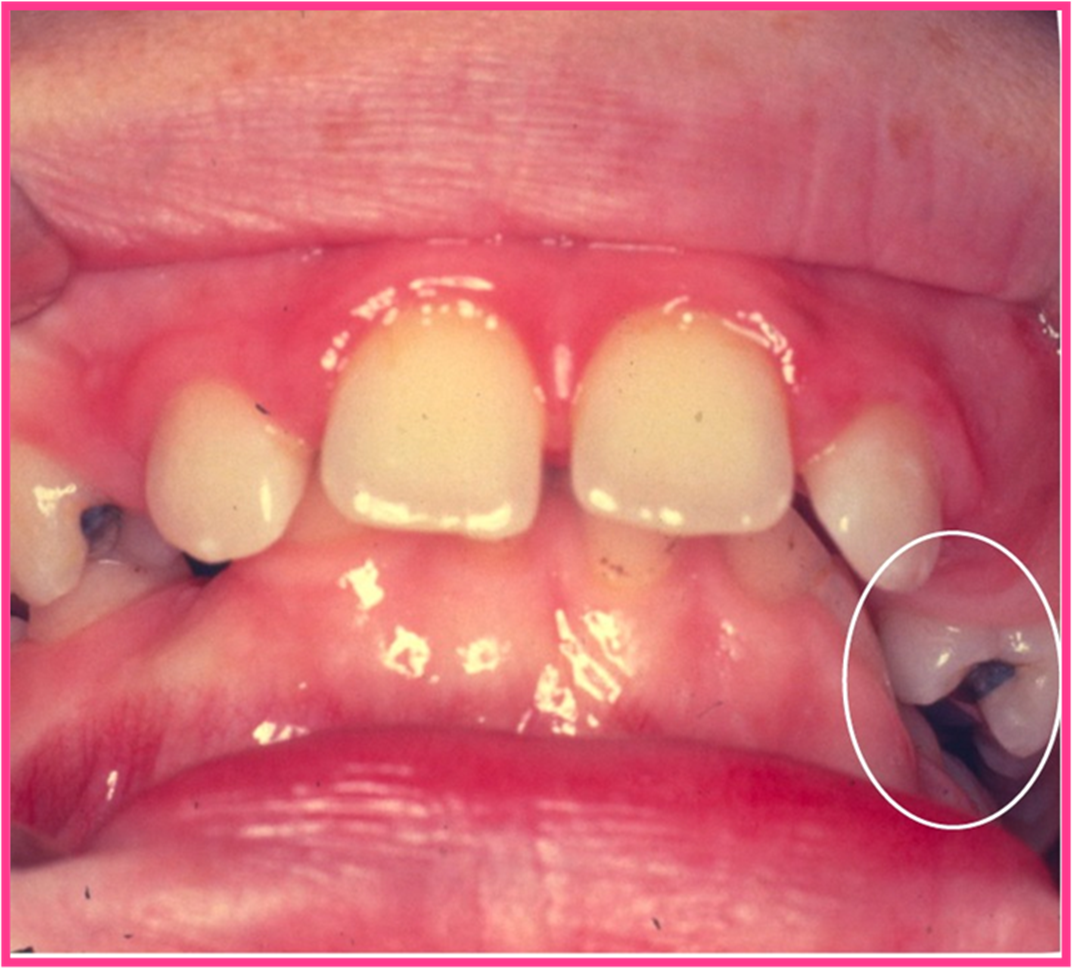

Saxbett bedöms kunna ha genetiska orsaker, men även muskelfunktion och andningsmönster kan påverka. Vid stor sagittal skelettal avvikelse med ärftlig orsak där mandibeln är retrognat eller maxillan prognat (postnormal avvikelse), så ockluderar underkäken per posteriort än normalt och en följd av detta kan bli saxbitning och vice versa vid prenormal avvikelse (3). (Bild 2)